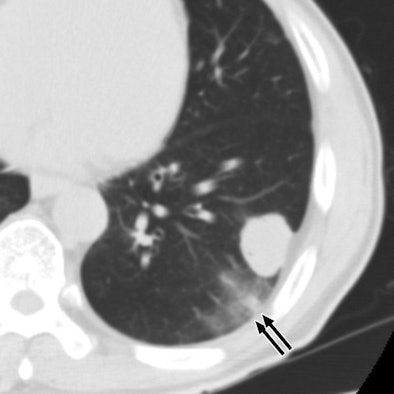

| 60-year-old man with metastatic squamous cell carcinoma from oral cavity. Above, axial CT scan obtained before tomotherapy shows mass (arrow) in left lower lobe, target lesion. Below, one-month follow-up CT scan shows focal ground-glass opacity (arrows) at periphery of target, representing radiation pneumonitis. |